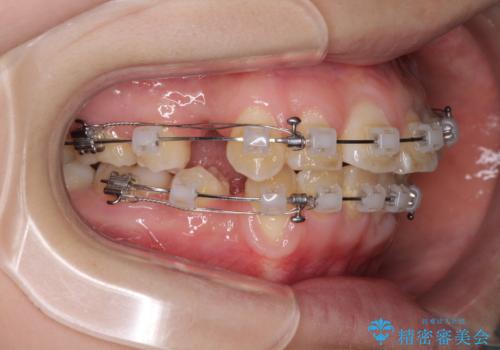

- クリアブラケット

- 2年1ヶ月

- 10-30回